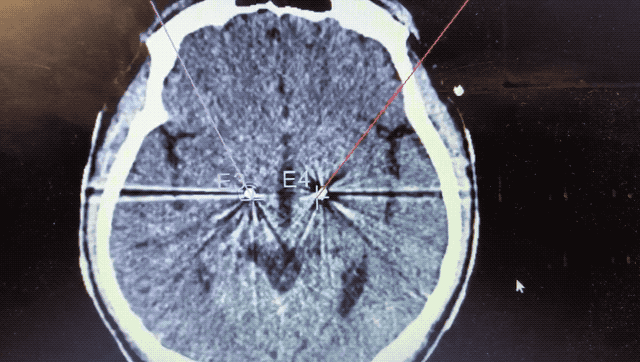

順利檢測到典型的核團(tuán)信號后,再次植入刺激電極到相應(yīng)位置,測試后即可完成單側(cè)的電極植入。對側(cè)只需借助機(jī)器人再次定位,并將檢測電極、刺激電極依次植入,最后,還需將刺激器植入患者胸前皮下。根據(jù)術(shù)后CT顯示,本手術(shù)雙側(cè)植入電極的位置與術(shù)前規(guī)劃路徑完全吻合,患者開機(jī)后,起搏器會開始沿刺激電極向患者核團(tuán)實(shí)施高頻電刺激,以減輕疾病癥狀,提高患者的生活質(zhì)量。

術(shù)后CT顯示雙側(cè)電極植入位置與規(guī)劃完全吻合